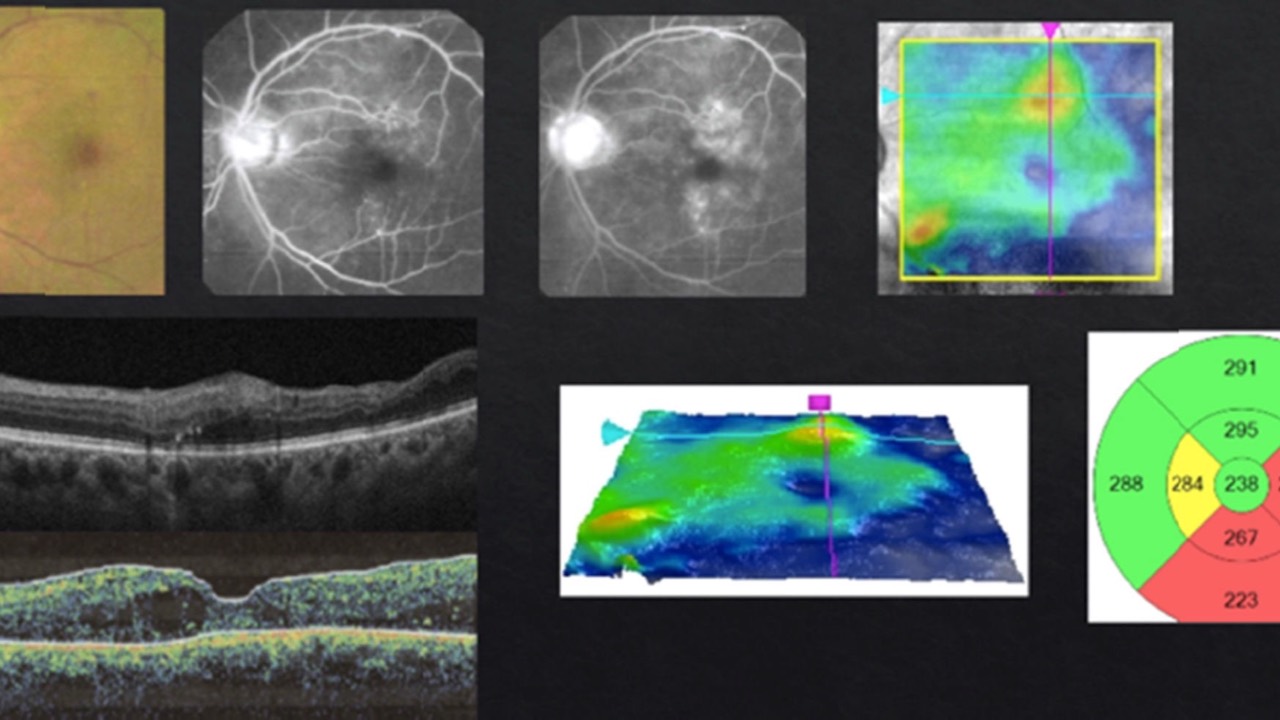

OCT Before Cataract Surgery

Yes or No?...

Optical coherence tomography (OCT) can be a valuable tool screening for hidden maculopathy prior to cataract surgery, offering us high-yield findings beyond traditional retinal exams and color photos.

It was recently shown around 21.5% of eyes cleared for cataract surgery with norm...